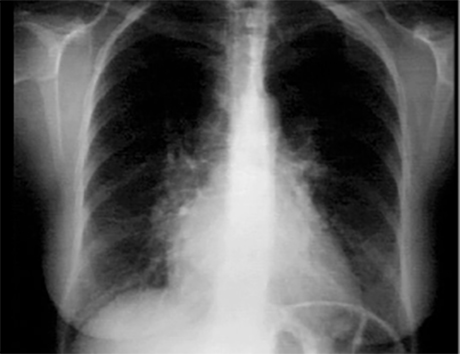

These chest X rays show right ventricular enlargement and left atrial enlargement.

The PA view demonstrates left atrial enlargement reflected by the

double contour within the heart border, an elevated

left mainstem bronchus and an enlarged

left atrial appendage causing straightening of the left heard border. Note also that the

cardiothoracic ratio is greater than 50%, reflecting cardiomegaly.